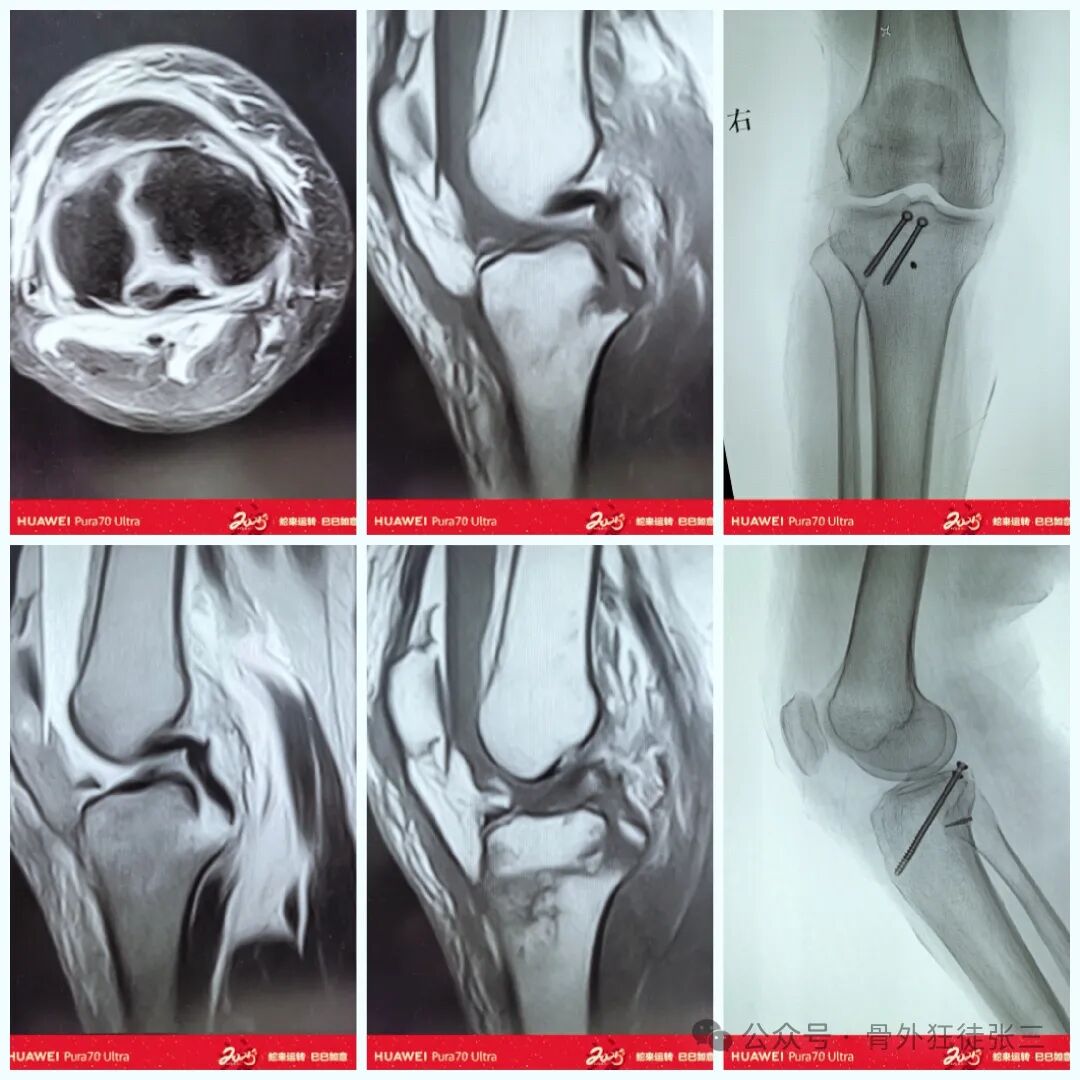

病例一

22岁警察,出警追人时不慎摔倒

使用1/3管型板塑形了一个勾板

铆钉收紧,钩板固定,双重保险